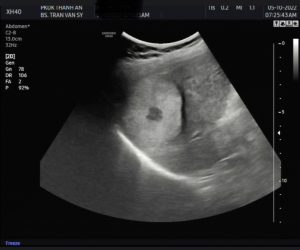

Hình ảnh ca Ung thư gan qua kĩ thuật siêu âm tại Phòng Khám điều đáng buồn là bệnh nhân còn quá trẻ và khối u có kích thướt đáng lo ngại.